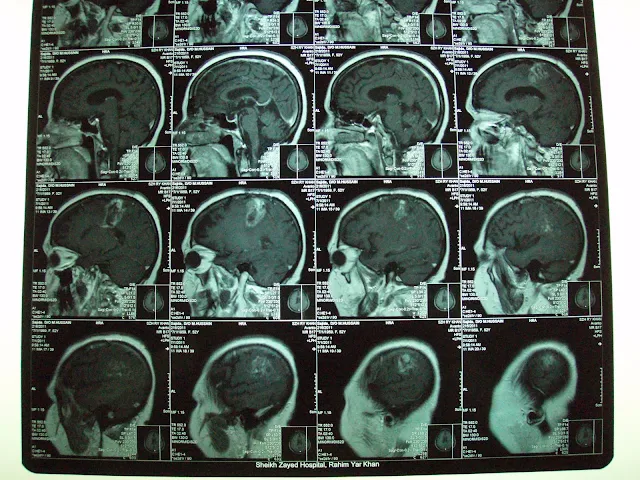

Ependymoma,complete resolution.

On referral, he had presented some improvement in headache and vomiting and significant improvement in blurring of vision. Clinical examination had revealed no obvious neurologic deficit. MRI brain spectroscopy had revealed markedly elevated Choline levels up to 399. Patient has referred us for the management with GKSRS. Risk of GKSRS explained all in Urdu along with requirement of strict follow up. These agreed upon wished to proceed. He had treatment with following prescription,

Multiple isocenters with 18, 14 & 8 mm collimator used in APS mode. He had discharged on tapering doses of Dexamethasone and advised follow up after 3 months